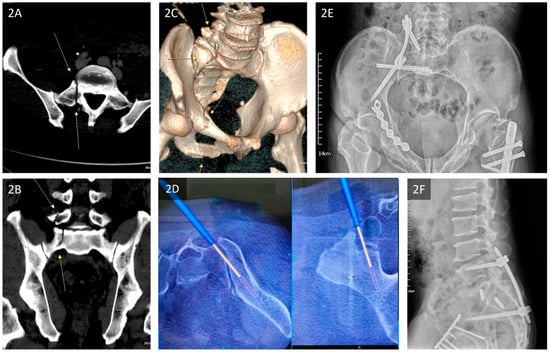

2.2. Radiographic Methods